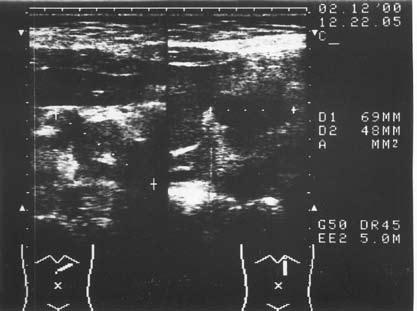

Ультразвуковое исследование (сканирование) является одним из наиболее информативных и притом неинвазивных методов исследования ПЖ и должно осуществляться во всех случаях, когда подозревается ее патология (рис. 137–139).

Датчик располагается в эпигастральной области и его перемещают соответственно проекции железы на области левого и правого подреберий. В норме ПЖ имеет ровные, четкие контуры и гомогенную структуру, а диаметр главного панкреатического протока не превышает 1,5–2 мм. При патологии может выявляться общее увеличение размеров органа с равномерным уменьшением эхоплотности, свидетельствующее об отеке. Уменьшение размеров железы, неоднородность структуры, наличие мелких участков уплотнения ткани, а также нечеткость контуров могут говорить о фиброзных изменениях в железе, а небольшие резко выраженные эхоположительные узелки – об очаговом обызвествлении паренхимы. Эхоструктуры высокой плотности, расположенные в протоке и дающие феномен «ультразвуковой дорожки», являются признаком внутрипротоковых конкрементов. Жидкостные образования (ложные кисты, вялотекущие абсцессы) представляются на эхограмме округлыми участками значительно пониженной эхоплотности с более или менее четкими контурами и дорсальным усилением. Хорошо сформированные ложные кисты с жидким содержимым имеют округлую или овальную форму, гомогенны и окружены четко выраженной капсулой. Содержимое несформировавшихся кист и абсцессов может быть неоднородным из‑за наличия в них, помимо жидкости, тканевых секвестров и детрита.

Рис. 137. Хронический панкреатит. Расширение протока поджелудочной железы (DP). L – печень; Р – поджелудочная железа; VL – селезеночная вена; IVC – нижняя полая вена; АО – аорта

Рис. 138. Хронический кальцифицирующий (калькулезный) панкреатит.

Кальцинаты в паренхиме ПЖ

Рис. 139. Хронический панкреатит. Конкремент в просвете протока ПЖ (DP)